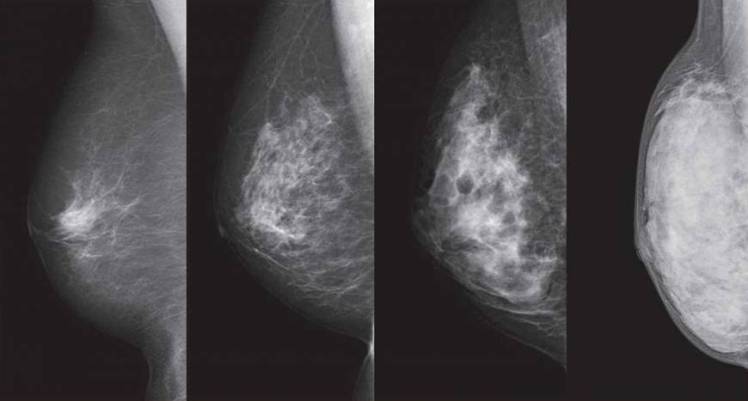

Radiologists reading our mammograms can determine if we have Dense Breasts. Breast Density is the single most important predictor of the failure of mammography to detect cancer. A small tumour would appear white on your Mammogram and Dense Breast tissue also appears white, so there is likely to be a ‘masking effect’ and a risk that a tumour will not be seen.

These mammograms show breasts with differing densities, (from left) ranging from an extreme fatty breast, one with scattered areas of density, a heterogeneously dense type and an extremely dense type. | NPO BREAST CANCER IMAGING NETWORK